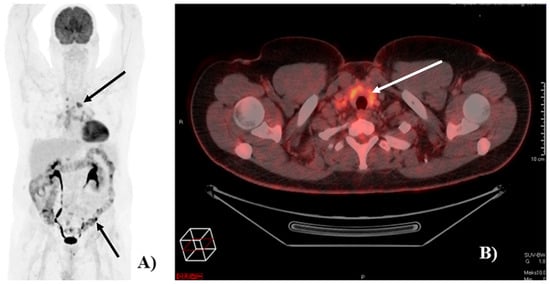

Of the 121 patients, 90 (74%) had at least one [18F]FDG-PET/CT detected irAE. Image examples of irAEs detected on [18F]FDG-PET/CT are shown in Figure 1.

Figure 1. Image of [18F]FDG-PET/CT-detected immune-related adverse events (irAEs). (A) Example of a patient with [18F]FDG-PET/CT-detected irAEs in the colon and in mediastinal lymph nodes (black arrows). (B) Example of a patient with [18F]FDG-PET/CT detected irAE in the thyroid (white arrow).

All patients received nivolumab; however, one switched to pembrolizumab due to an allergic reaction. Of the 90 patients with [18F]FDG-PET/CT-detected irAEs, 48 patients (53%) had more than one. As 6 patients had two irAEs in the same organ/organ system (5 in the GI tract and 1 in joints), the total number of irAEs identified on [18F]FDG-PET/CT was 165. The majority of irAEs (56%) were detected at the 3-month follow-up scan (Table 2).